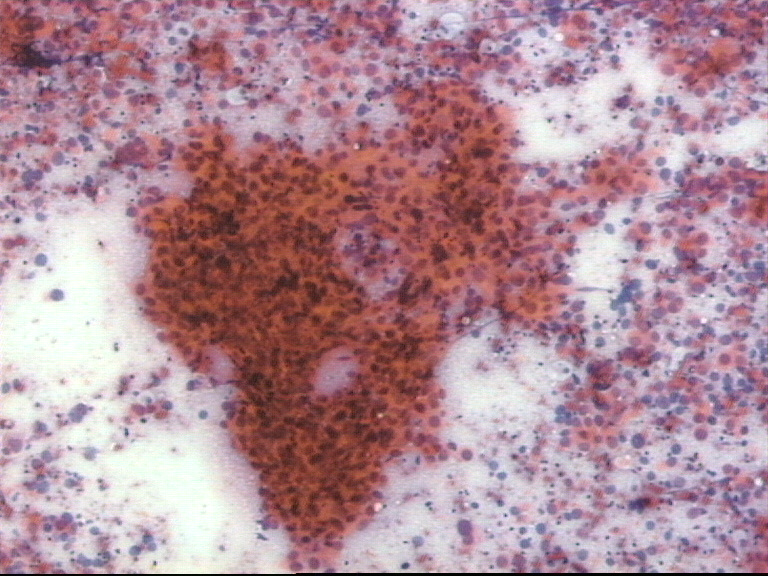

Figura 4.

Figura 5.

H/E por 100. Cilindros tisulares obtenidos de mama donde se muestra una lesión infiltrante de tipo lobulillar (4) y un carcinoma "in situ" comedo (5). Los cilindros de nódulos grandes pueden realizarse sin control radiológico pero los destinados a focos de microcalcificación requieren precisos instrumentos que identifiquen la lesión y que introduzcan el sistema de toma de muestra.